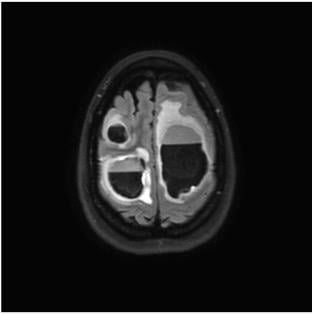

To study the hypothesis that radiation to the hippocampal stem cells plays a role in cognitive decline, 518 patients were randomized to whole-brain radiotherapy plus memantine with or without hippocampal avoidance. The results of the clinical trial found a 26 percent relative reduction in risk of cognitive toxicity following whole-brain radiation therapy with hippocampal avoidance versus whole brain radiotherapy. The cognitive function benefit of hippocampal avoidance did not differ by age.

By establishing that the hippocampal region is sensitive to radiation, treatment plans for brain metastases or other brain tumors can employ advanced techniques such as intensity-modulated radiation therapy (IMRT) or proton therapy to reduce dose to the hippocampus and offer brain therapy with less toxicity.

“Our phase III trial not only provides evidence for practice-change in the management of brain metastases, but also builds upon decades of preclinical and clinical research to definitely establish the hippocampus as a radiosensitive and cognition-specific organ at risk during brain irradiation,” said Gondi.